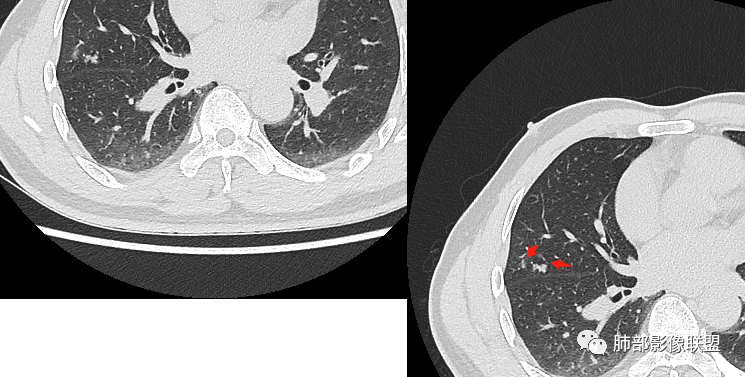

3.右肺中叶外侧段胸膜下散在小片影,磨玻璃密度为主,边界不清,支气管相关。符合炎性特征!

4.右肺下叶基底段支气管血管束旁小结节影,边界清楚,强化不明显。注意,这结节在“遥远的”基底段。

右肺中叶病灶

GGO,与支气管关系密切

这个形态、与支气管关系,与前两个不一致,所以考虑独立炎性病变。

3、卫星灶与“蘑菇兄弟”:诊断隐球菌时,建议找卫星灶,卫星灶可以在遥远的地方。可以是遥远地方的微小结节——“小蘑菇兄弟”。有些远处的卫星灶,通常是不规则饱满实性的,晕征不明显。隐球菌的卫星灶非常“隐”,但发现率高达60%多,诊断价值高。

4、卫星灶距离远的原因:隐球菌卫星灶常很远,推测:一次空气来源隐球菌感染进入双肺多处,部分定居繁殖;距离近的隐球菌“蘑菇兄弟”常常是二次感染。